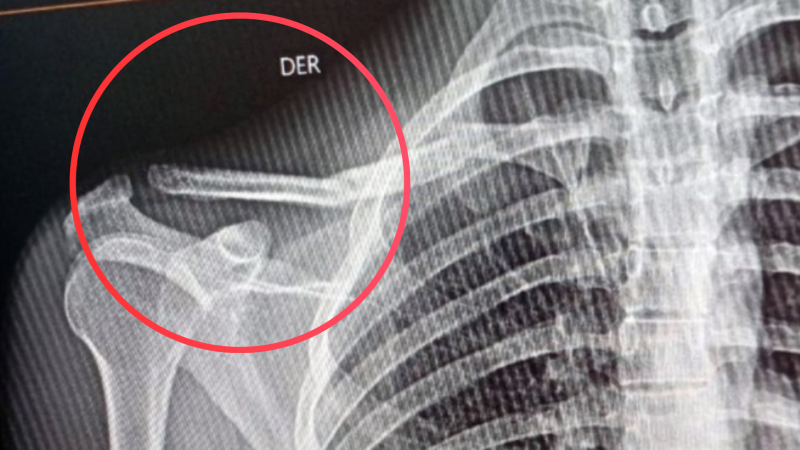

Una familia de barrio Raffo necesita de la solidaridad de todos. Tras un accidente vial ocurrido el sábado en Pilar, un joven rodriguense sufrió la fractura de su clavícula derecha en dos partes y debido a la difícil situación económica por la que atraviesan, se les hace imposible afrontar el valor de las placas anatómicas para que los huesos suelden correctamente.

Gustavo Molina Becker, de 20 años, estuvo internado hasta este lunes a mediodía en el hospital Vicente López y Planes. Ahora espera poder ser sometido a una intervención quirúrgica que le permita recuperar adecuadamente la zona afectada. La urgencia es que no puede pasar más de un mes o mes y medio porque si no, los huesos soldarían mal y los tendones se verían afectados por lo que perdería movilidad de su brazo, entre otros inconvenientes.

Gustavo precisa, de acuerdo a lo solicitado por el servicio de Cirugía Ortopédica y Traumatología del hospital, bajo el diagnóstico de Fractura segmentaria de clavícula derecha, realizarse una operación denominada Osteosíntesis de clavícula derecha.